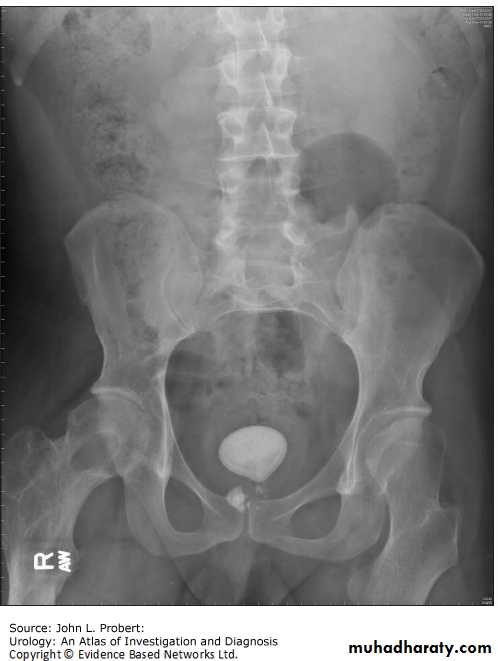

Urinary calculi

Nephrocalcinosis

Deposition of calcium salts in the medulla or cortex of the kidney.Medullary Nephrocalcinosis